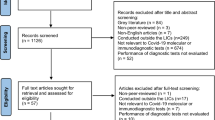

PubMed searches identified 1369 unique records for screening. The PRISMA flowchart of included studies is shown in Fig. 1. Studies that were excluded at the full-text stage are outlined (including the reason why they were excluded) in Supplementary Table 2. Data from the 16 studies that were relevant for inclusion, and their respective study characteristics, are outlined in Table 1. Study outcomes of the 16 included studies detailing correlation between SARS-CoV-2 real-time RT–PCR Ct values and epidemiological trends are summarized in Table 2, and as follows.